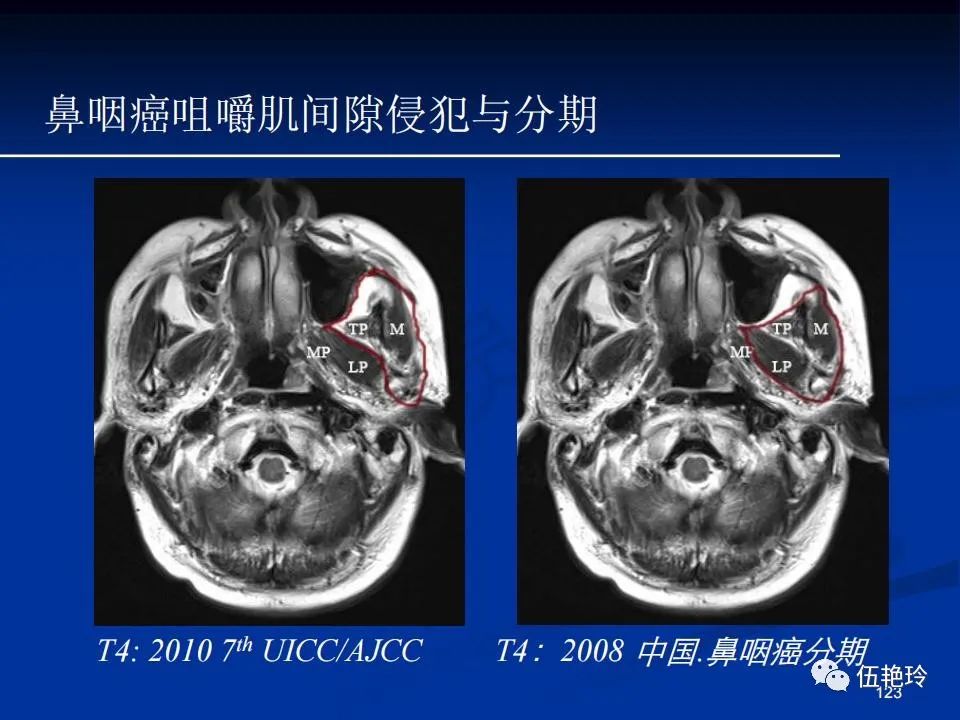

颞下窝与咀嚼肌间隙